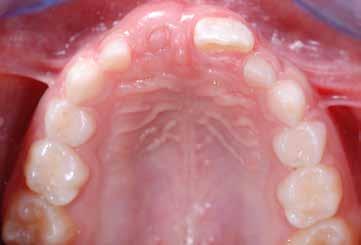

B.M. Bambina di sei anni e mezzo, con malocclusione scheletrica di II Classe, deep-bite over-jet elevato, lieve contrazione dell’arcata superiore, alterazione dell’eruzione dell’elemento dentale 21.

Fig. 125 > Immagine occlusale superiore.

Fig. 126 > Immagine occlusale inferiore.